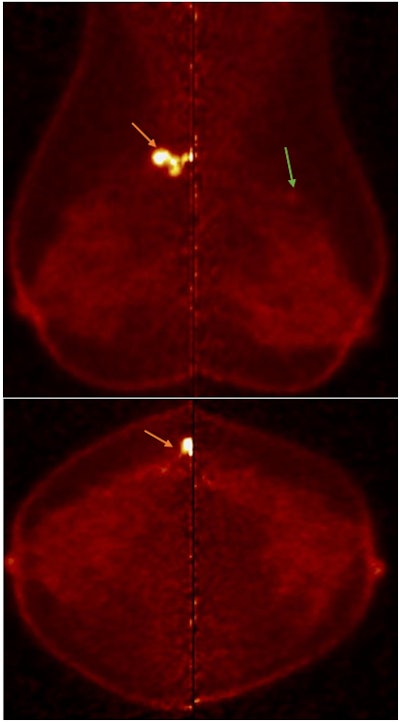

PEM detected contralateral malignancy missed in conventional mammography. Notably, there is a quantitative difference in uptake between both lesions, with the uptake of IDC in the right breast higher than ILC in the left breast. All figures courtesy of Dr. Aya Deabes et al and presented at EUSOBI 2025.